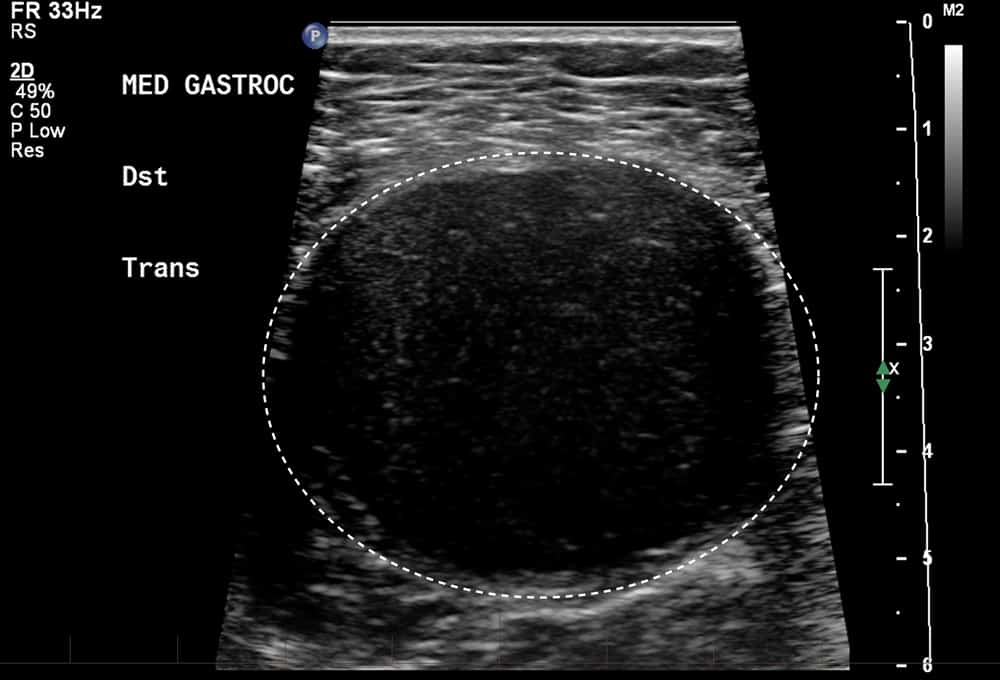

Tụ máu cẳng chân

Tụ máu cẳng chân - Ảnh 3

» Thông tin: Nam giới – 41 tuổi.

» Lâm sàng: Sưng đau cẳng chân / Chấn thương cẳng chân 15 năm.